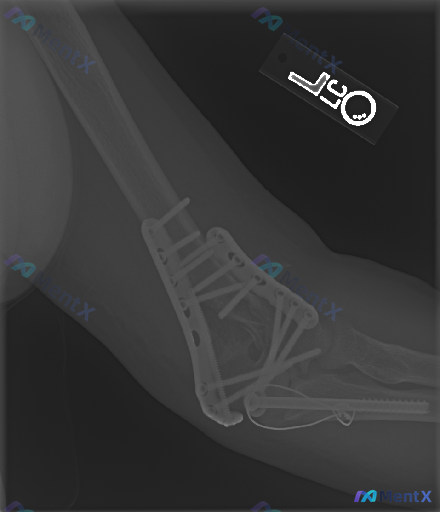

基本背景: 左肱骨远端+尺骨鹰嘴骨折切开复位内固定术后,复查侧位X光。

- 肱骨远端双钢板、尺骨鹰嘴张力带钢丝+长螺钉固定,位置尚可

- 骨折对位可,关节关系维持,未见明显脱位/半脱位

- 未见明显内固定断裂、松动征象

- 关节间隙未见明显狭窄,软组织仅见术后改变

如果只看这份常规报告,可能觉得“愈合得不错”。但结合这个提示,再回头看——金属伪影会不会掩盖了什么?